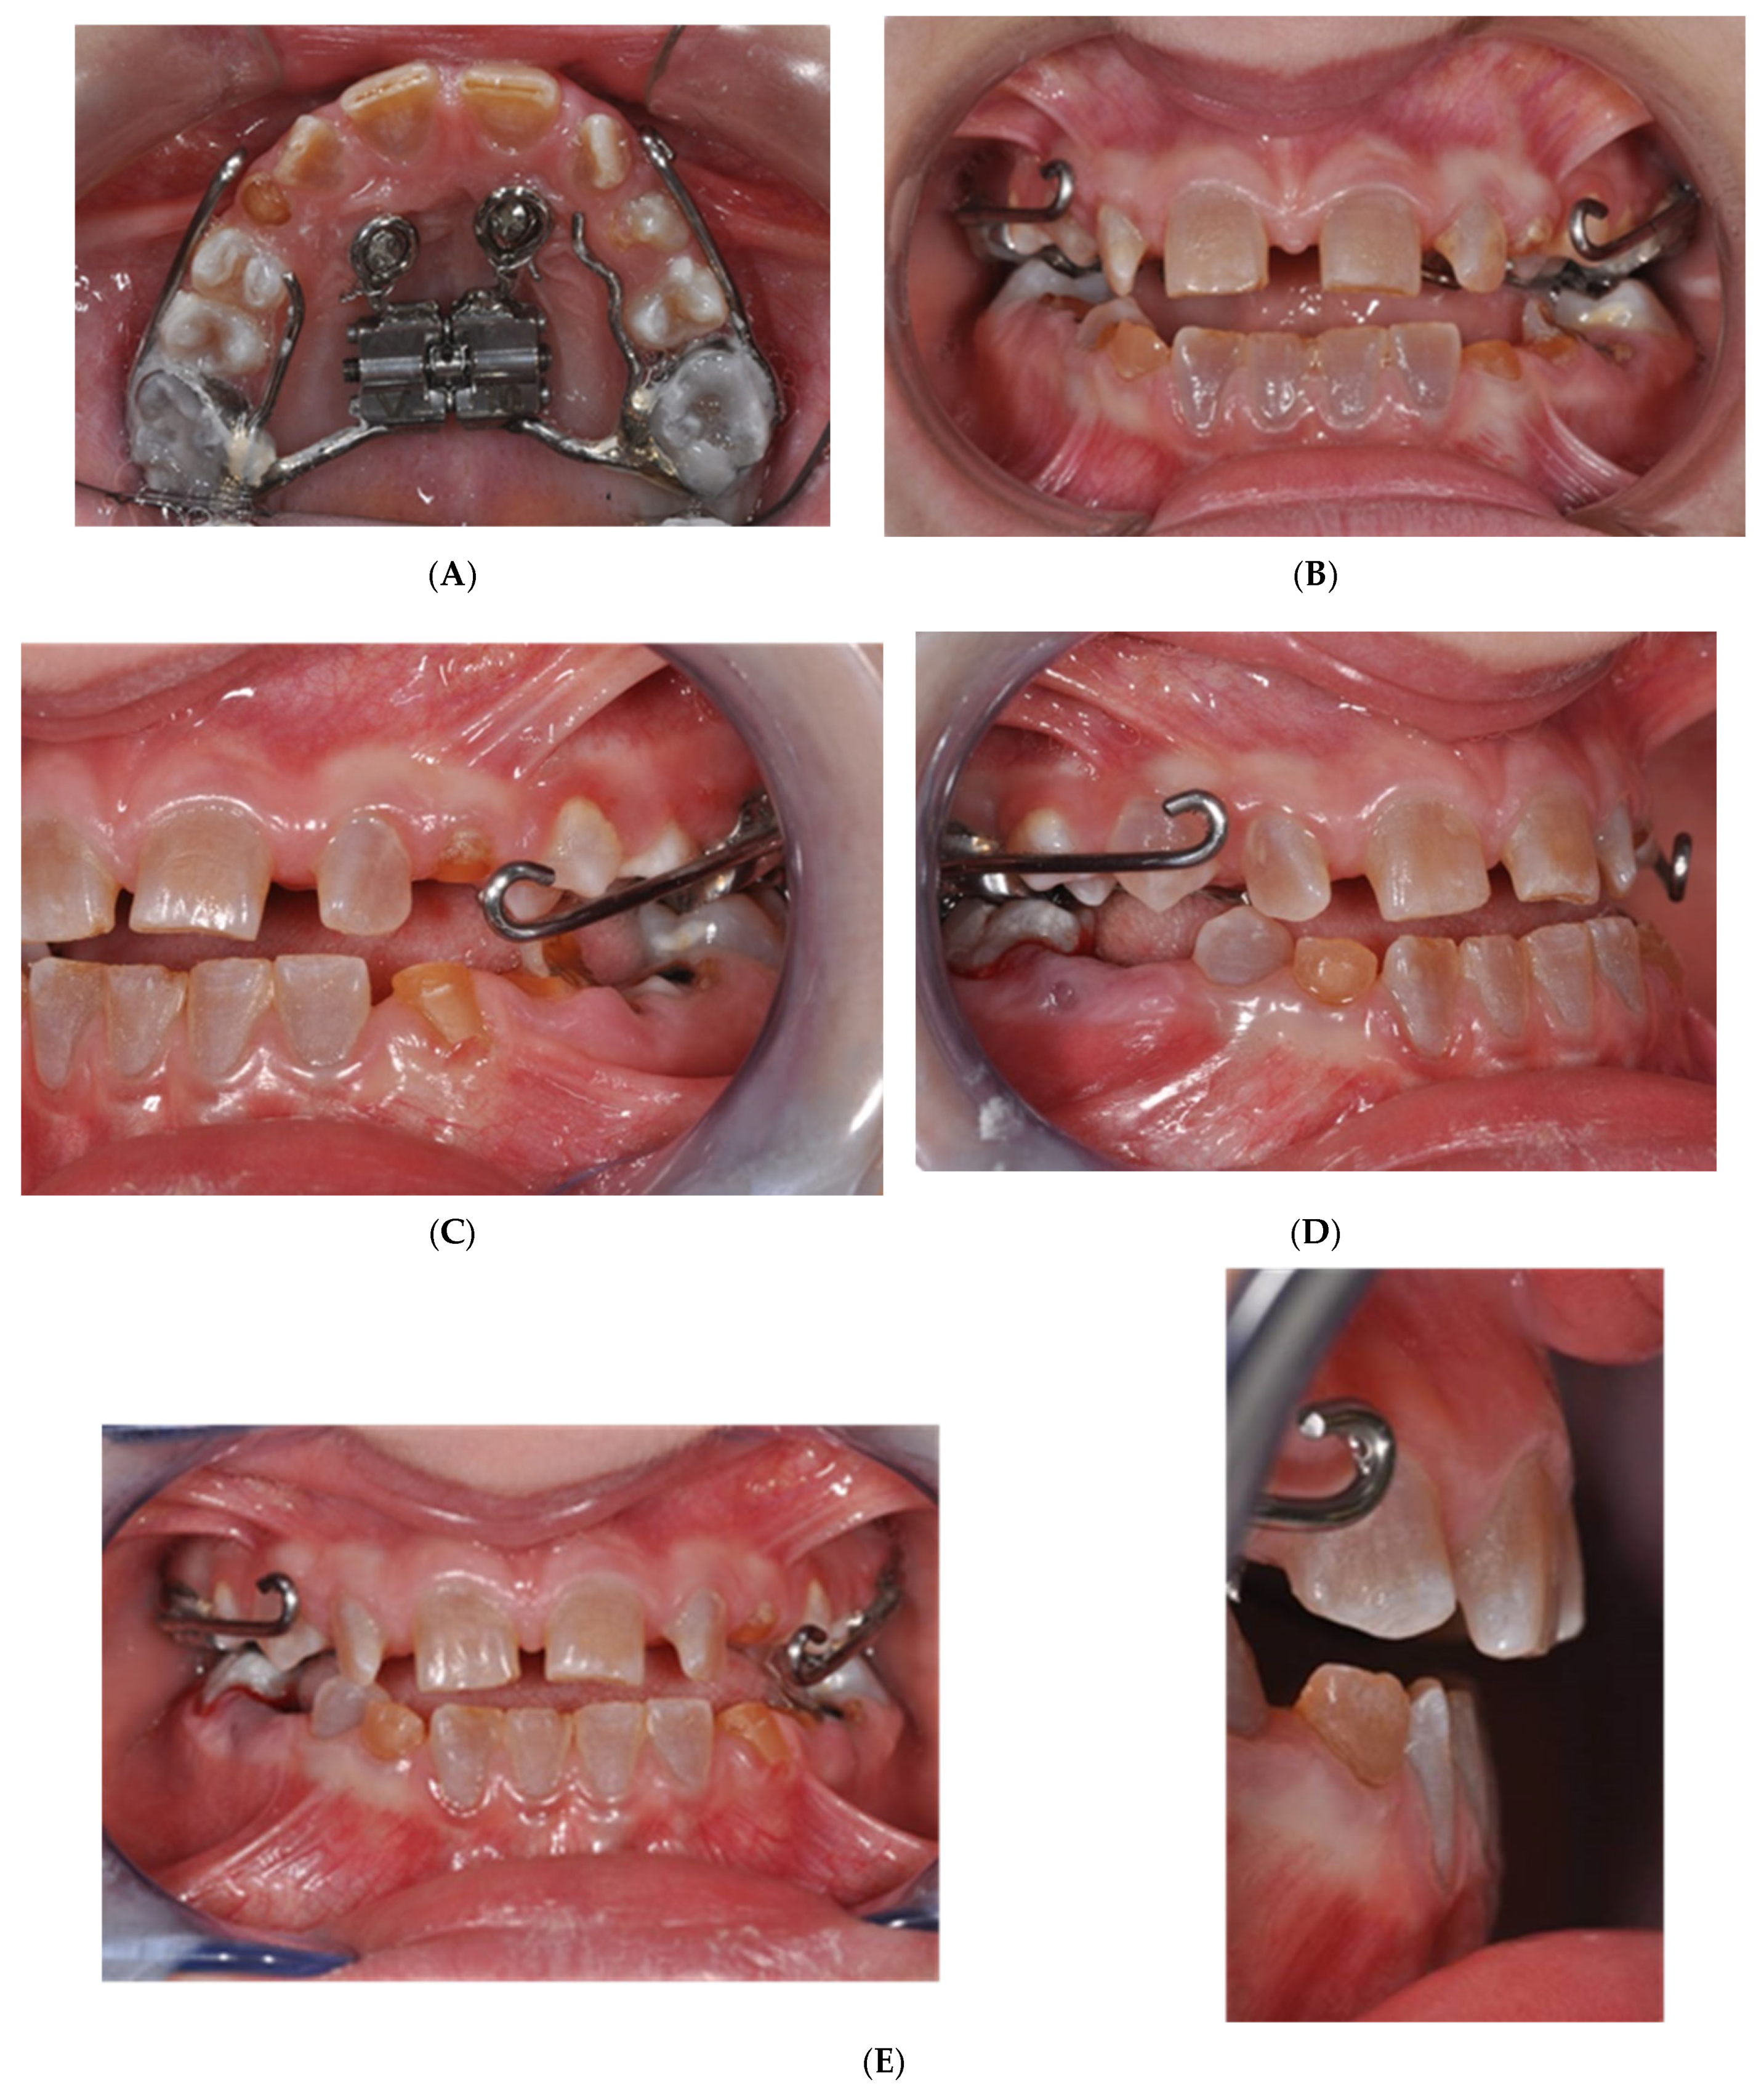

2.1. MSE Treatment in Patient with Ectodermal Dysplasia

2.2. MSE Treatment in Patients with Osteogenesis Imperfecta and Dentinogenesis Imperfecta